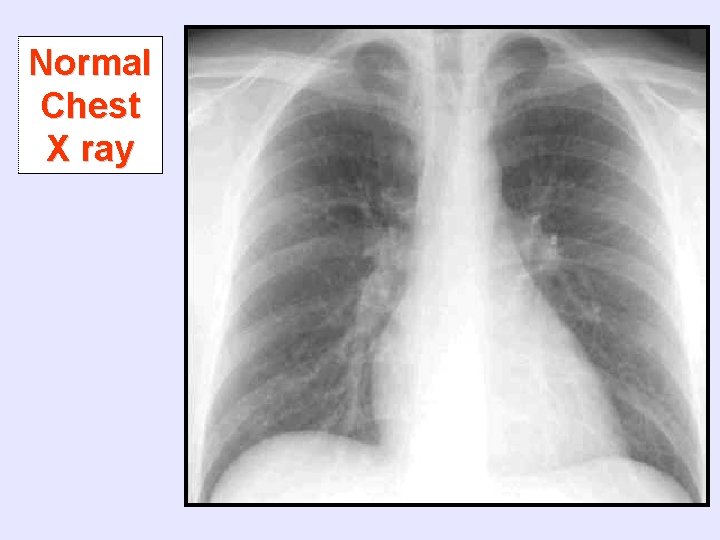

Normal Chest X ray